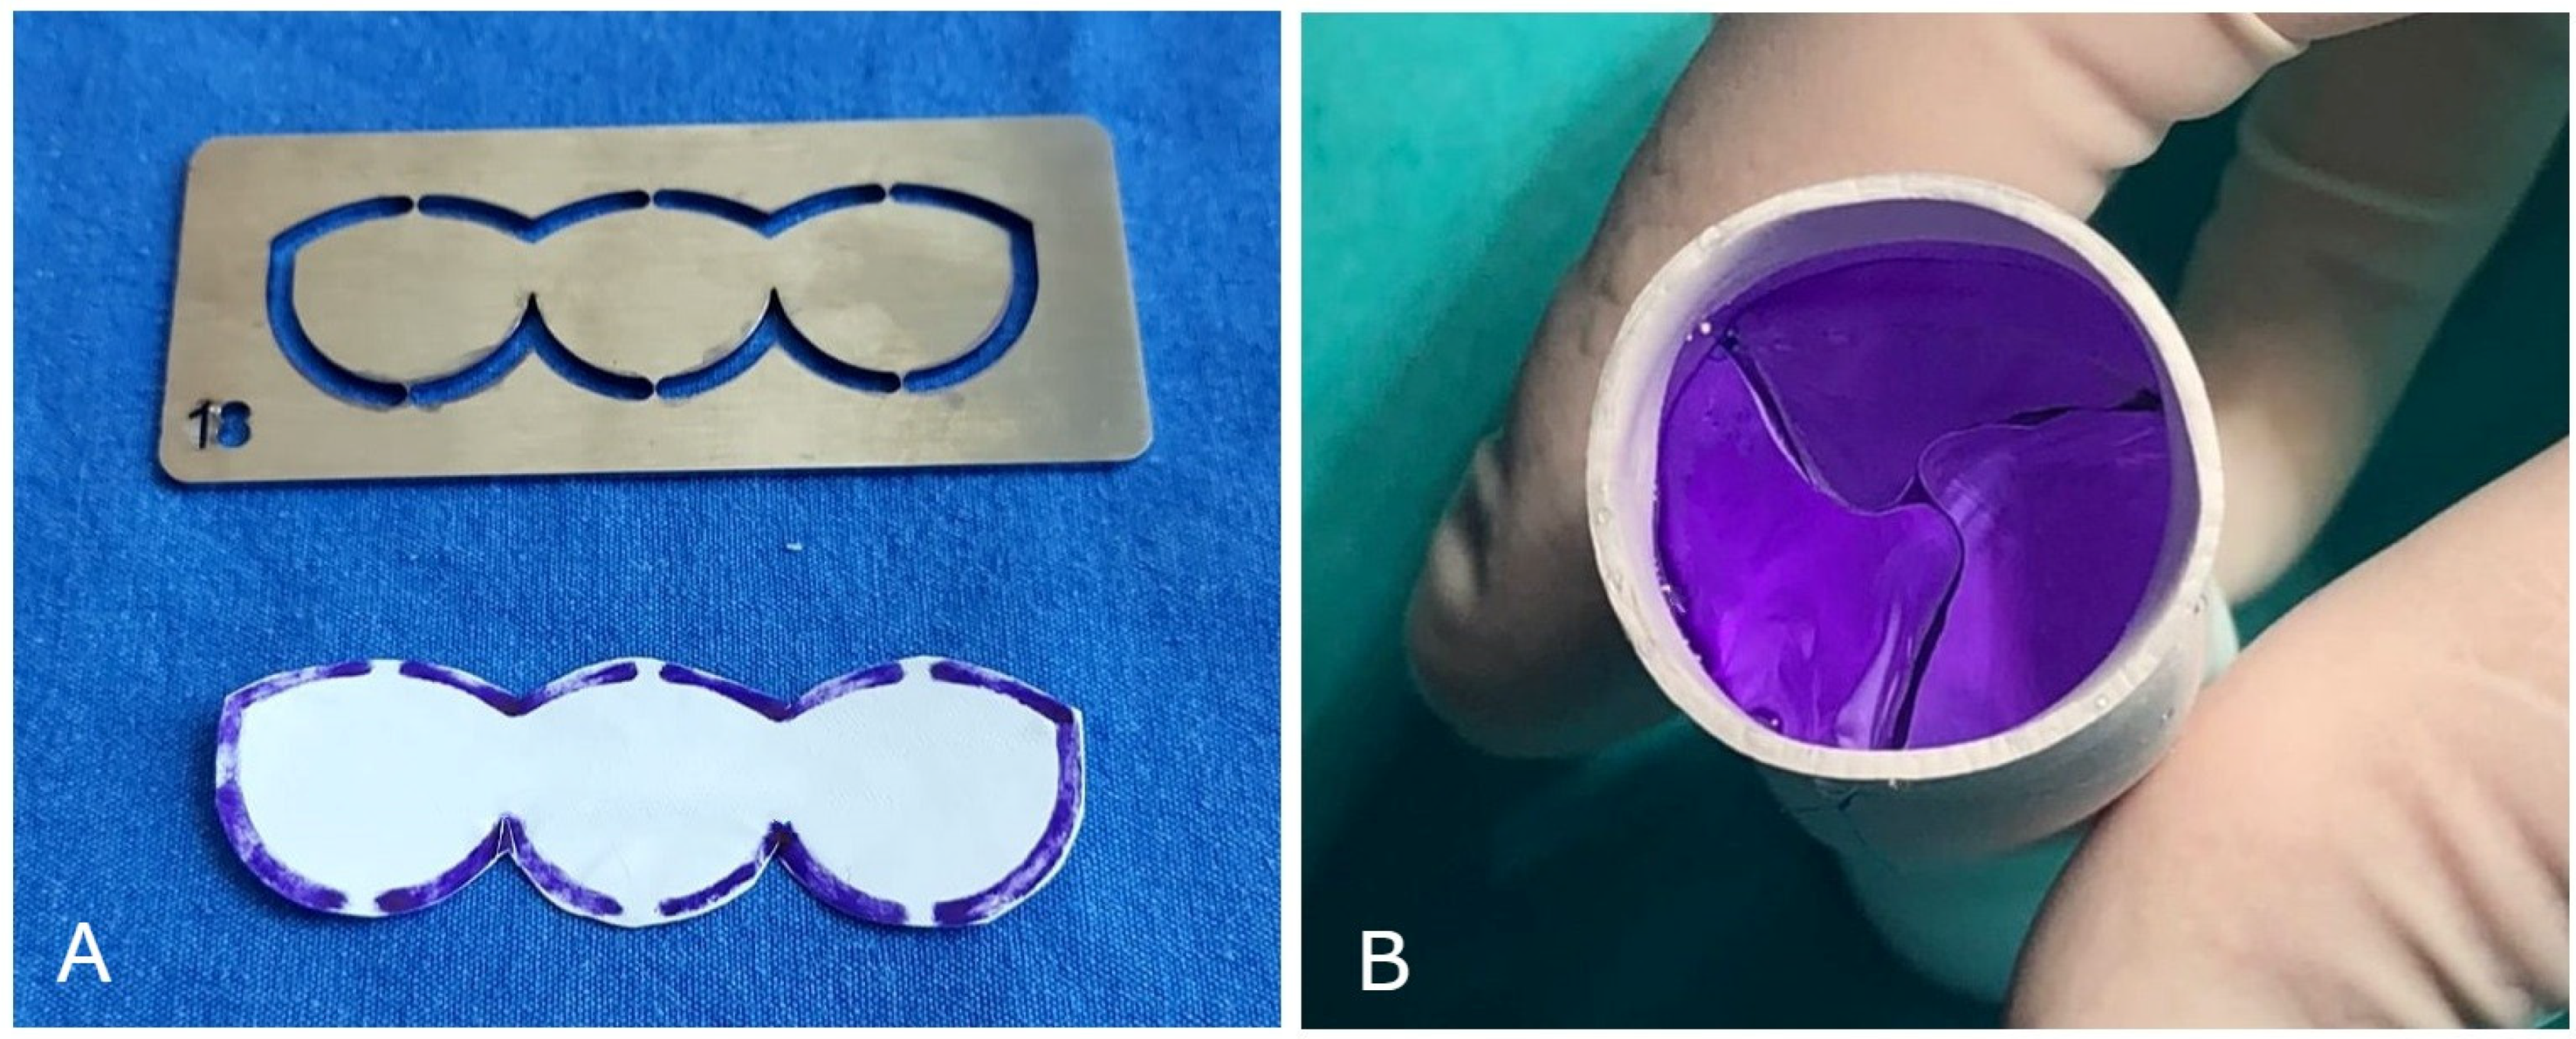

2.1. Surgical Technique